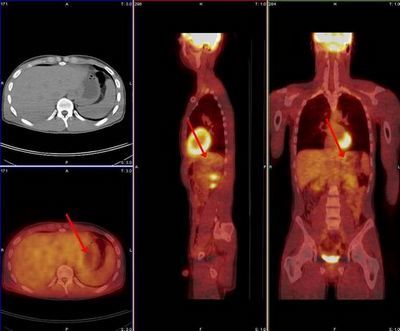

PET/CT检查:对于恶性肿瘤来说,这项检查是筛除全身扩散转移的重要工具,可以在疾病早期发现,但检查费用高。当普通的检查可以癌转移,但是表现不典型时,可考虑做作为补充诊断。临床应用受到限制

。